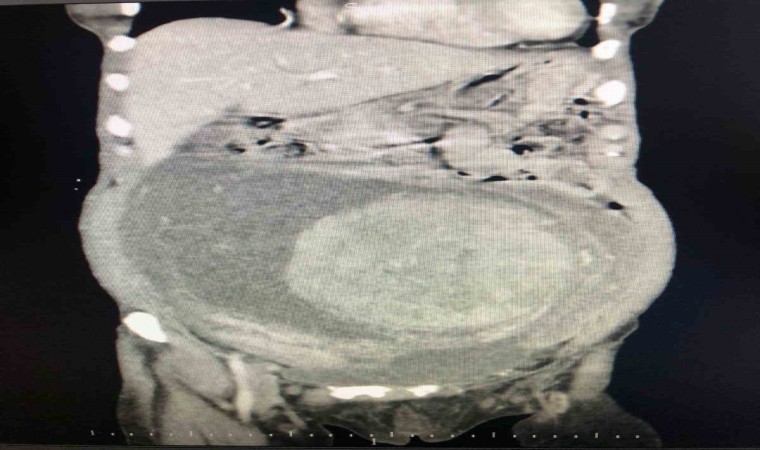

Tokat Devlet Hastanesi’nde görevli Genel Cerrahlar Operatör Doktor Ahmet Topcu ve Orkun Subaşı, Hicran Işık tarafından gerçekleştirilen başarılı ameliyatla, Işık’ın yumurtalıklarından 30x25 santim boyutlarında ve 6 kilogram ağırlığında kitle çıkarıldı. Ameliyatın ardından Hicran Işık sağlığına kavuştu.